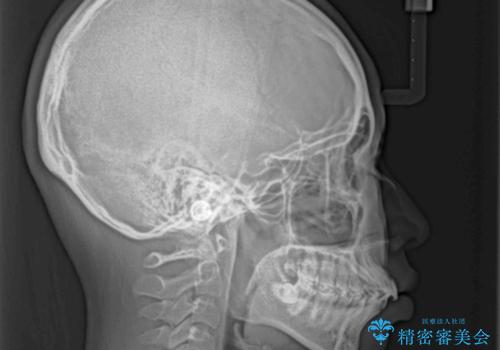

- 下唇に跡がつくほどに飛び出した上顎前歯を気にして来院された患者様です。

来院された時から4本の抜歯が必要であることを理解されていらしており、通法通り上下左右の第一小臼歯4本を抜歯し、ワイヤー装置にて矯正治療を行うこととしました。

順調に治療が進み、2年弱で想定していたとおりの仕上がりにて治療を終えることができました。